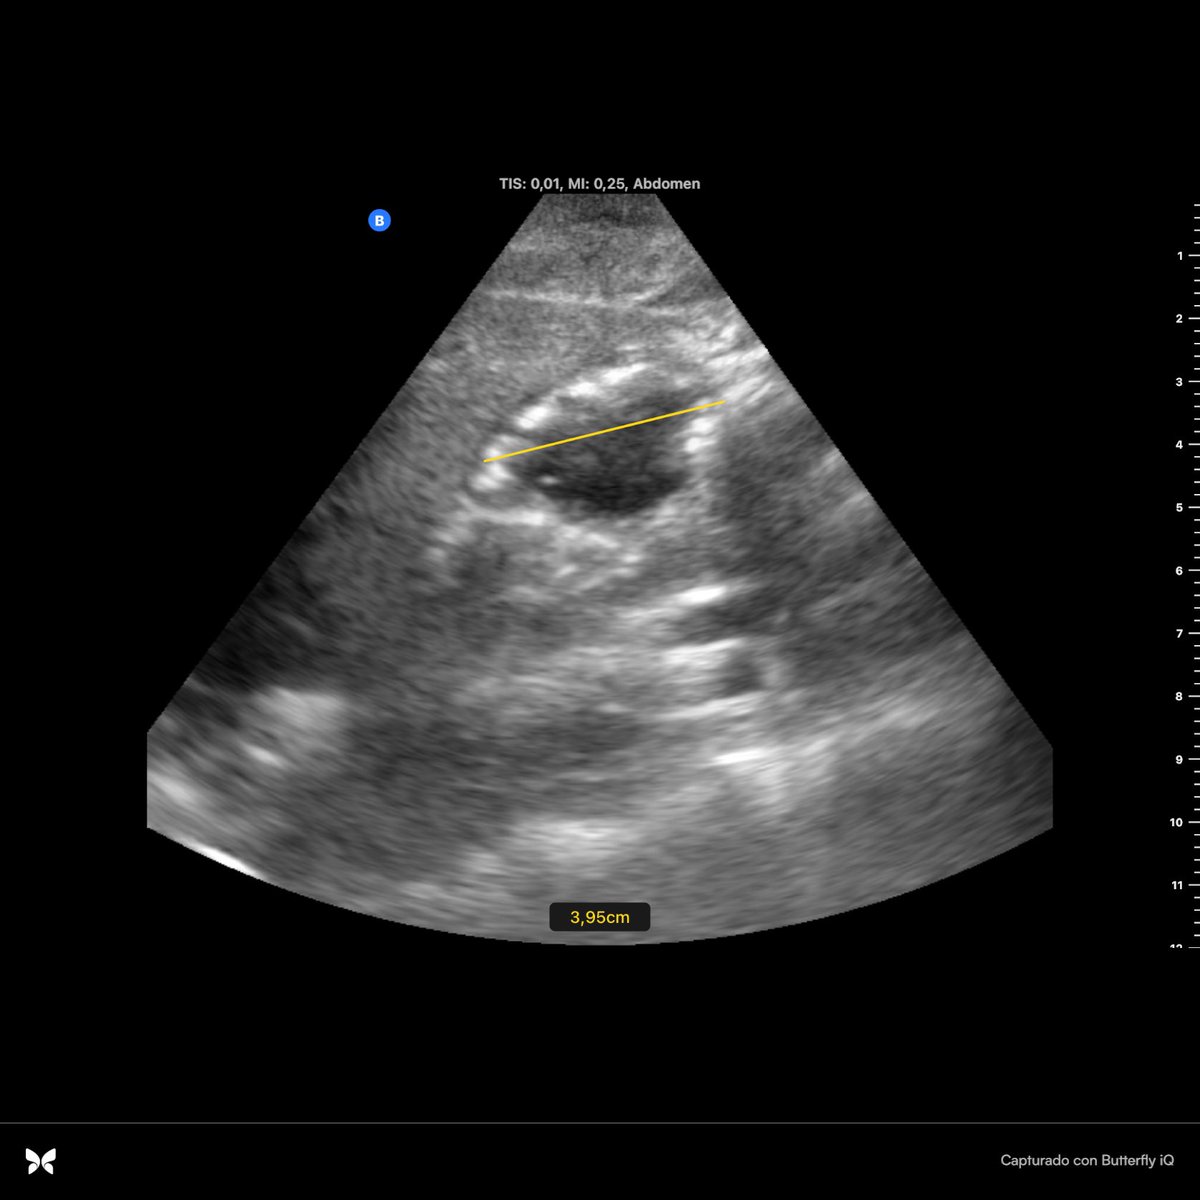

Mujer de 60 a. Ant : DM . Acude con dolor abdominal , fiebre y signos de hipoperfusión . ( I ) ( II / zoom ) Imagen anecogénica de bordes irregulares dentro de parenquima hepático : Absceso hepático #Pocusfirst #EM #PAUSE